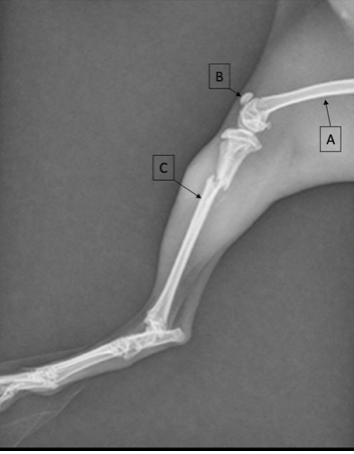

Identify the labeled structures

A = femur

B = patella

C = fibula

D = tibia